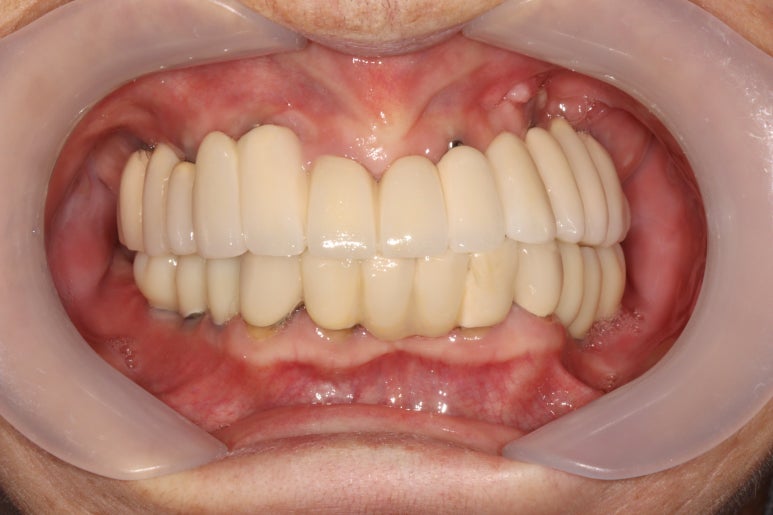

생각보다 임시치아보다 훨씬 매끈한 표면과 비슷한 색깔을 자랑하는 지르코니아 크라운입니다.

아마 어금니에 임플란트가 생긴건가? 싶으실거에요.

오스템 원가이드 네비게이션 임플란트 시스템을 이용하면, 정교하게 이상적인 위치에 임플란트를 심어낼 수 있어 자연스러운 임플란트 보철물을 제작하는데 많은 도움을 받을 수 있습니다!!

최종 완성된 보철물은 상당히 이상적인 형태를 갖고 있습니다.

이제 드디어 부분틀니를 쓰지 않아도 되는 ... 행복한 순간입니다.

차이를 별로 못느끼실 수 있겠지만, 임플란트 보철물 완성 6개월 후 방문 때 구강내 사진입니다.

감사히도 환자분께서 상당히 깨끗하게 유지하고 계셔서, 잇몸에 염증하나 없이 너~무 보기 좋더라구요.